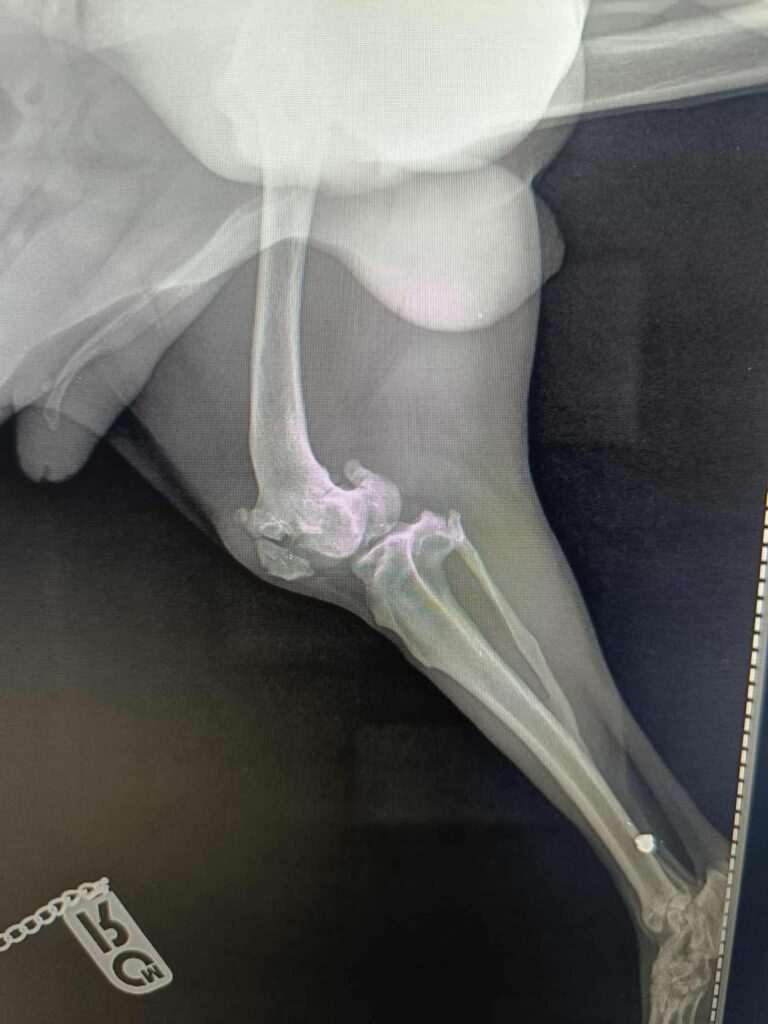

Hij werd aangereden en brak zijn poot.

Niemand deed daar wat aan dus hij heeft daar maanden of misschien wel langer mee rondgelopen.

Inmiddels is de breuk oud en is er niets meer aan te doen.

Roby heeft ook resten van kogels in zijn poot en bekken dus er is ook nog op hem geschoten .